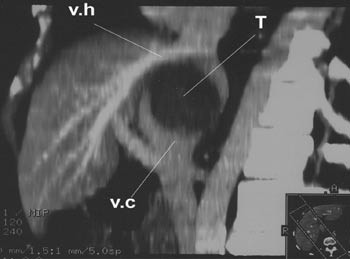

Pasient 1. 64 år gammel mann som ble utredet ved lokalsykehus for ukarakteristiske magesmerter. Ved abdominal CT var det blitt påvist en 6 x 6 x7 cm stor tumor beliggende mot leverens bakside, muligvis i segment 1. V. cava var sterkt komprimert og på det nærmeste okkludert av denne tumoren (fig 1). Tumoren ble initialt oppfattet som et leverneoplasme. Grunnet relasjonen til v. cava ble tilstanden ansett som utilgjengelig for kirurgi, men pasienten ble henvist til Rikshospitalets Seksjon for gastroenterologisk kirurgi til vurdering (second opinion). Biopsimateriale fra tumoren ble av ett laboratorium med et visst forbehold beskrevet å være fra et leiomyom. Et annet laboratorium mente det dreide seg om et schwannom. Antatt risiko for forestående okklusjon av vitale leverkar samt en sannsynlighet for at det dreide seg om et malignt neoplasme gjorde at man ble enig om å forsøke kirurgisk fjerning av tumor. Rutinemessige preoperative blodprøver viste normale verdier (e-tab 1).

Operasjonen ble utført 30.4. 2001. Etter mobilisering av leveren fikk man god tilgang til neoplasmet, som viste seg å være totalt adherent til v. cava i et område som strakte seg fra levervenenes innmunning i v. cava kranialt til innmunningen av venstre nyrevene kaudalt. Å løsne neoplasmet fra v. cava viste seg ikke å være mulig. Det ble da anlagt ekstrakorporeal veno-venøs bypass til v. brachiocefalica fra høyre v. femoralis og fra v. mesenterica inferior (7), og leveren ble tatt ut sammen med neoplasmet og den retrohepatiske v. cava etter at leverkarene og gallegangen var fripreparert og avsatt. Leveren med tilhørende vev ble straks plassert på et sidebord, hvor den ble lagt i iskjølt saltvannsløsning og perfundert med standard preservasjonsløsning (8). Heller ikke ex situ var det mulig å løse neoplasmet fra v. cava. Hele v. cava med neoplasmet ble derfor fjernet fra leveren (fig 2). V. cava ble så erstattet av en 22 mm goretexprotese, og de tre levervenene ble koblet til denne protesen, som vist i figur 3. Leveren ble deretter brakt tilbake til pasienten hvor vaskulær rekonstruksjon ble gjennomført som ved regulær levertransplantasjon (9). Leveren ble revaskularisert etter at pasienten hadde vært anhepatisk i 4 timer og 43 minutter. Den veno-venøse bypass ble avsluttet og gallegangen ble rekonstruert ved en ende-til-ende-anastomose.

Pasient 2. 29 år gammel kvinne som de siste tre år hadde merket økende bukomfang og ubehag i abdomen. Hun hadde gjentatte ganger konsultert lege for dette før hun ble innlagt i lokalsykehus til utredning for anemi. Det ble der konstatert at pasienten hadde en meget stor levertumor, hvorpå hun ble overflyttet til Rikshospitalet. Hun hadde da et bukomfang som ved langtkommet graviditet. Nedre kant av tumor kunne palperes nedenfor umbilicus. CT (fig 5) viste at det dreide seg om en ekstremt stor levertumor, et sannsynlig hemangiom, som inntok hele venstre leverlapp, inkludert segment 4. Høyre leverlapp var flatklemt ut mot flanken. Den retrohepatiske del av v. cava var tilsynelatende okkludert, og et utstrakt nett av kollateraler ble påvist. Preoperative laboratorieprøver er vist i e-tabell 2.

Operasjonen ble utført 18.11. 2002. Etter konstruksjon av veno-venøs bypass ble den ekstremt forstørrede leveren (fig 6) eksplantert sammen med tilhørende del av v. cava. På sidebordet ble så hele neoplasmet ekstirpert (e-fig 7). Den resterende del av leveren (segment 5 – 8) ble deretter lagt tilbake i pasienten og revaskularisert som skissert i figur 8. Pasientens v. cava var i mellomtiden blitt erstattet av en ca. 10 cm lang goretexprotese med diameter 22 mm. En preoperativt diagnostisert, men ubehandlet stenose i a. coeliaca antas å ha vært en disponerende årsak til trombosering i leverarterien. Den ble påvist ved ultralydkontroll neste morgen.